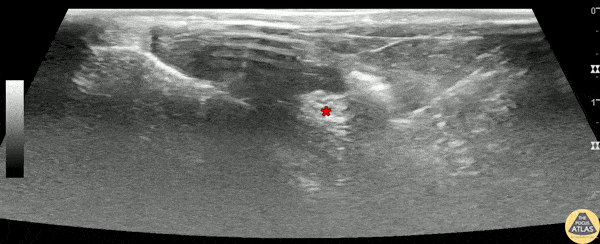

60s M presented with foot/toe pain in the setting of recent freeze/thaw frostbite. To aid in analgesia, a posterior tibial nerve block was performed. The block is shown here, with the needle entering from the posterior/medial aspect, depositing local anesthetic adjacent to the tibial nerve (*). The patient had improvement of his pain and was subsequently able to be discharged. Dr. Tyler Prince, PGY1 Denver Health Residency in Emergency Medicine Dr. Nimish Bhatt, Fellow Denver Health Ultrasound Fellowship